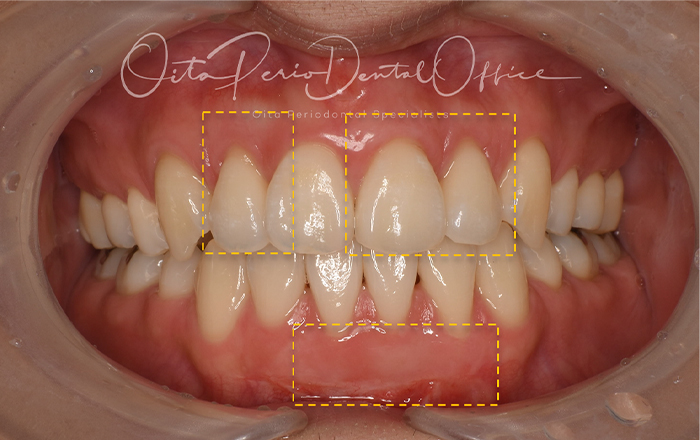

| 治療期間 | 6週間 |

|---|---|

| 治療費 | 24万 |

| 治療内容 | 上顎前歯部根面被覆術、下顎前歯部遊離歯肉移植術 |

| 治療のリスク | ドナーサイトが必要、 術後の疼痛・腫脹、術後の注意事項をフォローしない場合は失敗の可能性あり |